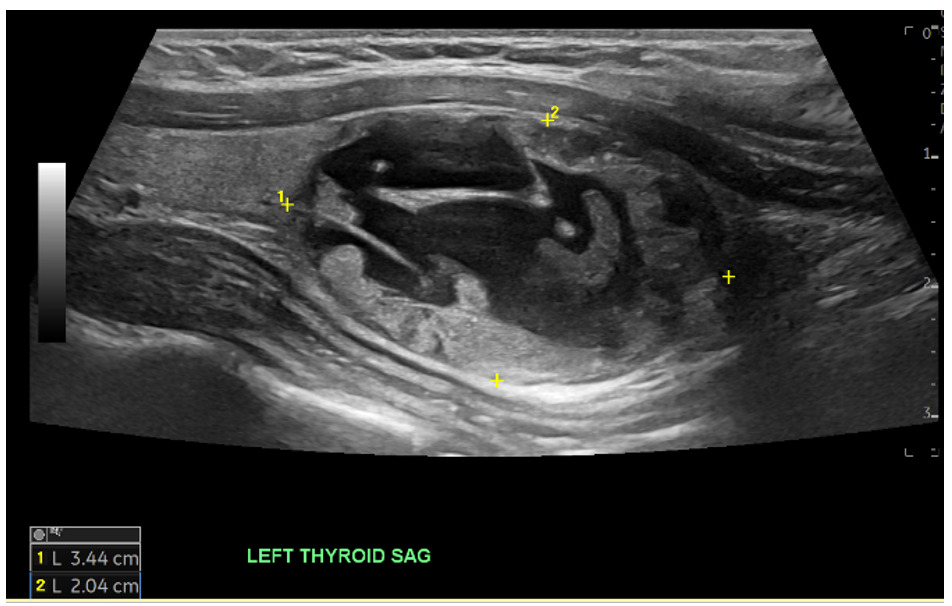

A thyroid ultrasound demonstrated a large cystic and solid nodule in the left thyroid measuring 3.4 cm in largest dimension categorized as TR 3 as well as a right thyroid nodule categorized as TR 4 per Thyroid Imaging Reporting & Data System (TI-RADS) criteria (Figure 2). Labs showed no significant abnormalities.